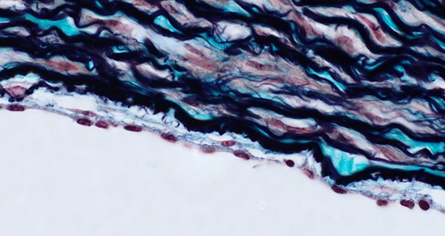

The patient is referred for an

ultrasound examination of the right carotid artery after the examination

reveals a significant murmur in it. The murmur is not audible either in the

left carotid artery or in the heart; the ultrasound confirms that the murmur is

caused by a significant atherosclerotic plaque that has already narrowed the

right carotid artery significantly, causing turbulent blood flow in the

narrowed area and a murmur audible by phonendoscope. Atherosclerotic plaque is

formed by lipid deposition in the tunica intima and its further inflammatory

transformation. What layers does the tunica intima consist of in a healthy

person?

View this question